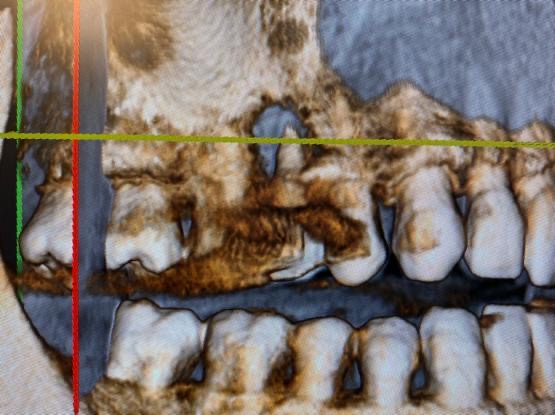

Dalla radiografia 3D, in questo caso, è emersa una situazione completamente differente. Il paziente presentava una reazione infiammatoria con riassorbimento dell’osso periradicolare, probabilmente di origine traumatica o endodontica.

Grazie alla ConeBeam sul paziente è stata effettuata prima una estrazione e poi la conseguente rigenerazione ossea con biomateriali e membrana, che consentirà, poi, l’inserimento di un impianto.